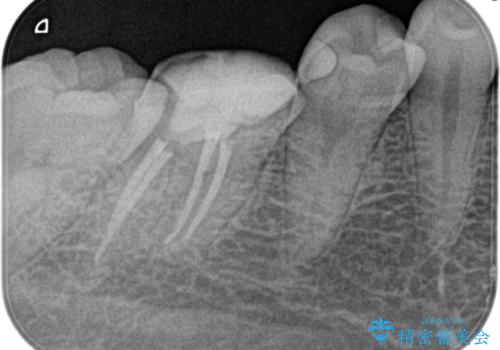

- 奥歯がズキズキ痛いことを主訴に来院されました。

検査の結果、診断を症候性不可逆性歯髄炎、症候性根尖性歯周炎とし抜髄を行っております

根管充填はhydraulic condensation techniqueにて行なっております。

シーラーはWell pulp ST 使用